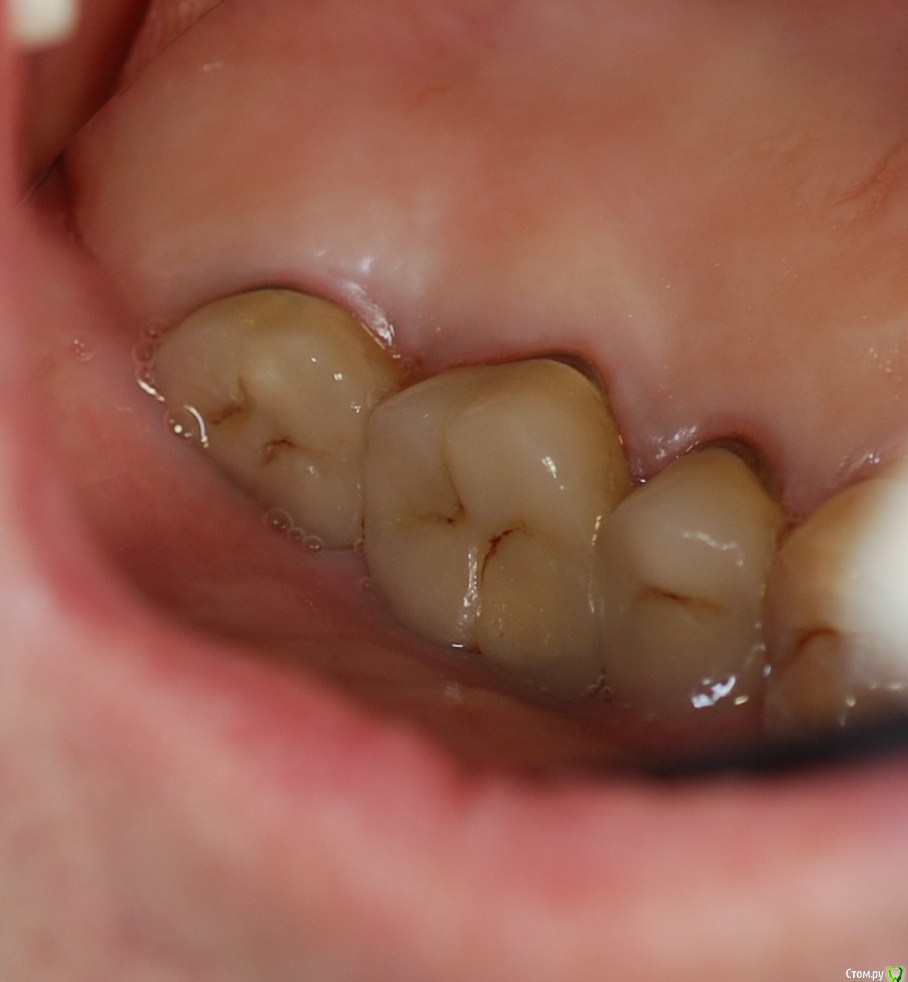

Популярный пост carloss Опубликовано 3 декабря, 2015 Популярный пост Поделиться Опубликовано 3 декабря, 2015 http://savepic.su/6646447.jpg http://savepic.su/6630063.jpg сегодня http://savepic.su/6681262.jpg http://savepic.su/6664878.jpg http://savepic.su/6619823.jpg http://savepic.su/6658734.jpg без чисток и тд.. десять лет вообще не ходила к стоматологу 31 Ссылка на комментарий

carloss Опубликовано 3 декабря, 2015 Автор Поделиться Опубликовано 3 декабря, 2015 (изменено) Можно подробнее, сделали ампутацию? да, раньше часто делал, но обычно срезал один из щечных корней.. большинство стоит до сих пор, правда тут, и шестерка и пятёрка экстремально без феррула, кроме ампутации тока вот, чтобы не обольщались - антагонисты, концевой бюгель)) Изменено 3 декабря, 2015 пользователем carloss Ссылка на комментарий

Doc Опубликовано 6 декабря, 2015 Поделиться Опубликовано 6 декабря, 2015 Через много лет плохой гигиены и жуткого прикуса, 20 июля 2012 года. 9 Ссылка на комментарий